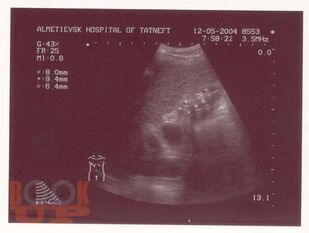

В учебном пособии представлены современные методы лечения ЖКБ. Рассмотрены как хирургические, так и консервативные способы. Показаны их преимущества и недостатки. Также отражены распространенность, патогенез, клиника и диагностика данного заболевания. Пособие предназначено для врачей-терапевтов, врачей общей практики, гастроэнтерологов, врачей скорой помощи, абдоминальных хирургов, интернов, ординаторов.